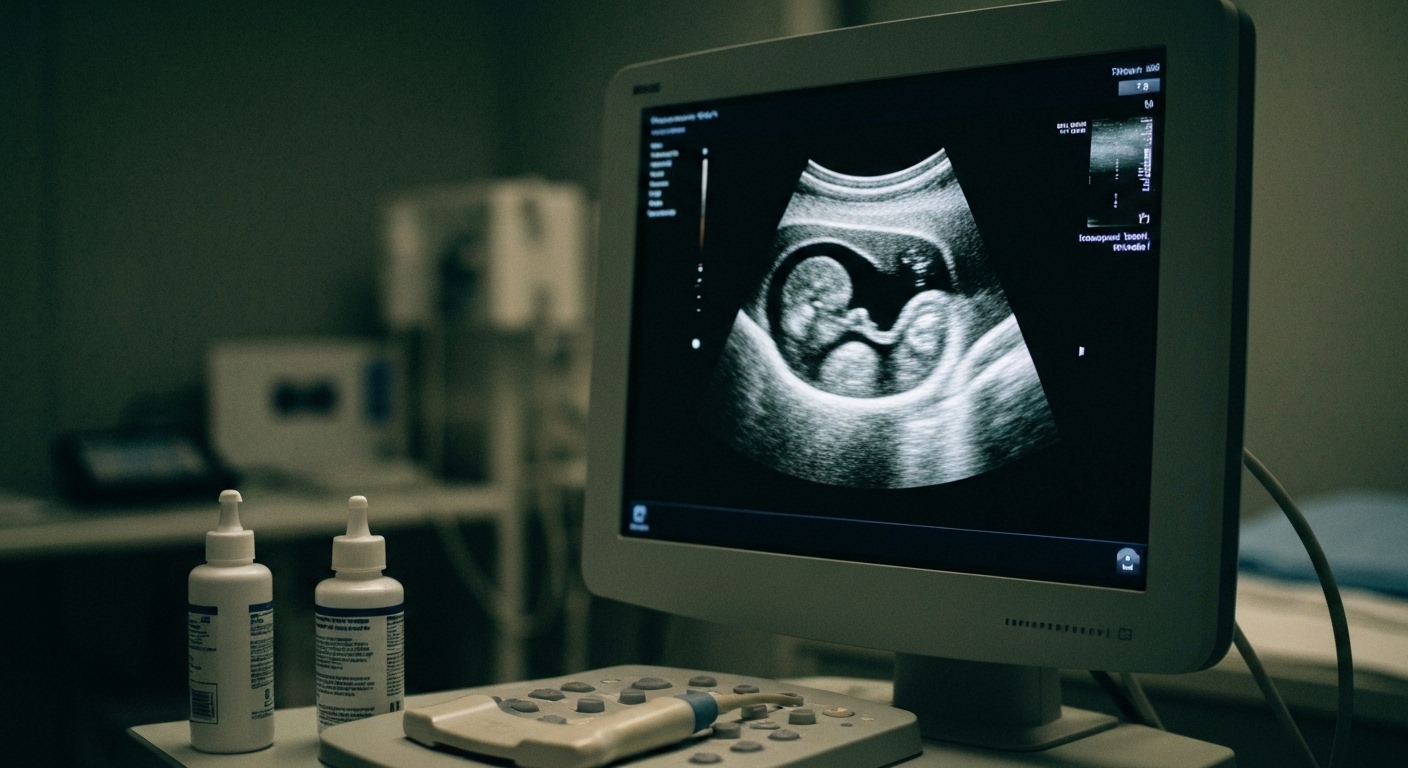

The researchers evaluated two key metrics of healthcare engagement to determine how medication patterns influenced clinical follow-up: the foregone routine prenatal ultrasound served as the primary outcome, while the foregone postnatal examination was analyzed as the secondary outcome. These screenings represent critical touchpoints for identifying fetal anomalies and managing maternal recovery, yet the data revealed significant gaps in attendance among women using antidepressants. When comparing the broad cohorts, 18.6 percent of the antidepressant-exposed group forewent prenatal ultrasound, whereas only 13.2 percent of the comparison group (those with no psychoactive medication use) missed this screening. This trend of decreased engagement extended into the postpartum period, with 26.6 percent of the antidepressant-exposed group foregoing the postnatal examination compared to 21.4 percent in the comparison group. To ensure the robustness of these findings, the authors employed generalized estimating equation models (a statistical framework that accounts for correlations within data, such as when a single woman contributes multiple pregnancies to a dataset). This analysis adjusted for several potential confounders, including maternal age, the specific year of the pregnancy, and the individual identity of the women. The most pronounced risk was identified in the subgroup of 135 women who resumed medication after an initial cessation. In this restart group, 77.0 percent of women forewent their prenatal ultrasound, a figure that stands in sharp contrast to the 13.3 percent missed rate observed across the entire study sample. This resulted in an adjusted odds ratio of 22.43 (95% CI = 15.00 to 33.53, p < .001), suggesting that the clinical instability or symptom recurrence that necessitates restarting an antidepressant is a powerful predictor of missed routine prenatal care.

The most striking finding of the study centered on the subgroup of women who resumed antidepressant therapy after an initial period of cessation. Among the four medication patterns analyzed, restarting antidepressants was the only pattern significantly associated with foregone prenatal ultrasound. This specific clinical trajectory appears to serve as a potent marker for healthcare disengagement. While the overall sample of 69,938 pregnancies showed a baseline rate of 13.3 percent for missed ultrasounds, the figures for the restart group were markedly higher. Specifically, 77.0 percent of women in the restart group forewent their routine prenatal ultrasound, representing a substantial departure from standard obstetric care protocols. Statistical analysis using generalized estimating equation models confirmed the magnitude of this association. The researchers calculated an adjusted odds ratio of 22.43 for foregone ultrasound in the restart group, with a 95 percent confidence interval ranging from 15.00 to 33.53 (p < .001). This 22-fold increase in the odds of missing a critical screening suggests that the clinical circumstances leading to a medication restart, such as a relapse of depressive or anxious symptoms, may simultaneously impair a patient's ability to attend scheduled appointments. For the practicing clinician, these data indicate that the timing of antidepressant discontinuation and subsequent resumption is a critical indicator of potential gaps in prenatal monitoring. The stark contrast between the 77.0 percent missed rate in the restart group and the 13.3 percent rate in the entire sample underscores the need for targeted outreach and integrated mental health support when a pregnant patient requires a re-initiation of pharmacotherapy.